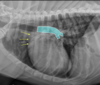

18

What is shown in this image?

A

arteries, bronchi, and veins in lateral view

-arteries are dorsal to bronchus

-veins are ventral to bronchus